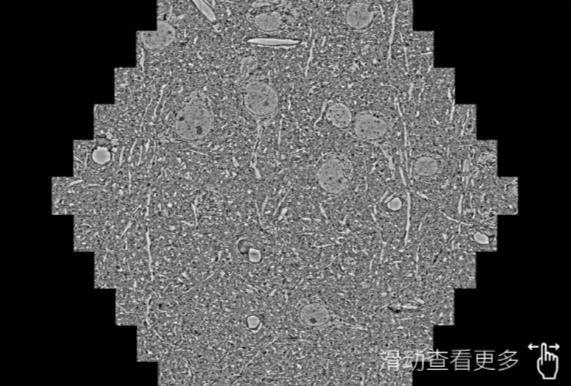

鼠脑切片。左图使用梅州蔡司梅州扫描电镜MultiSEM706对165μmx143pm面积区域成像,耗时仅需1.5秒。右图为鼠脑切片中30μm区域放大效果。样品由芝加哥大学B.Kasthuri提供。

使用蔡司高速梅州扫描电镜MultiSEM对1mm²人脑皮层组织进行高分辨成像,并对其中的各种细胞结构进行三维重构分析。左图展示了2x3mm²组织平面中锥体神经元的三维重构效果。右图显示了局部体积神经元三维重构。图像由哈佛大学chtman实验室提供,渲染图由D. Berger 制作。